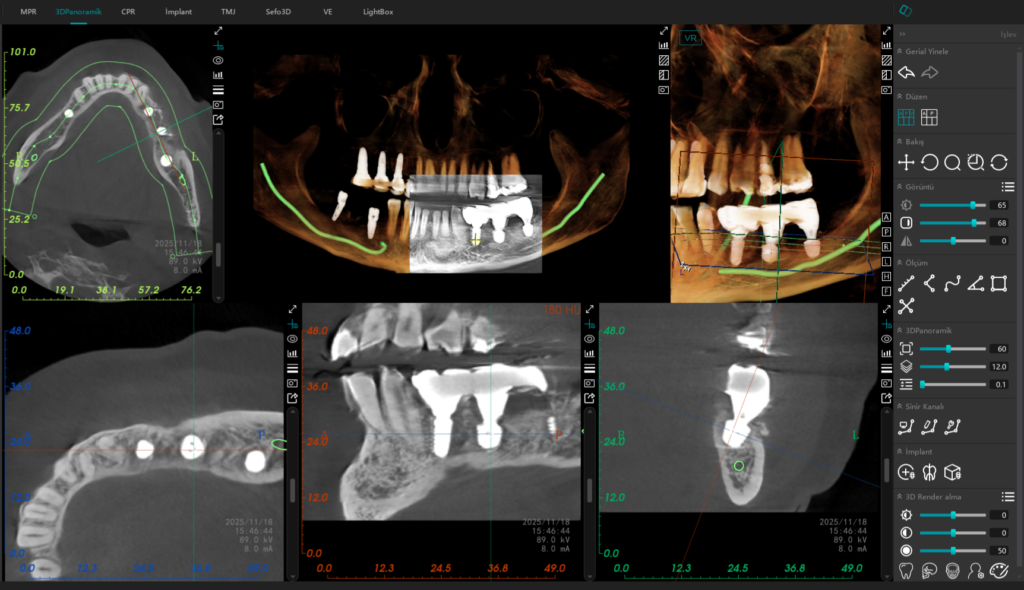

Alt çenede ana sinir kanalına olan mesafe kısıtlı (5-6 mm) olduğunda, geleneksel uzun implantlar büyük bir risk teşkil eder. Bu vakada, Alman mühendisliğinin güvenilir çözümü olan Bredent short (kısa) implantları tercih ettim. Bu özel tasarım implantlar sayesinde, sinir kanalına güvenli bir mesafede kalarak, hastamızı olası bir his kaybı riskinden tamamen korumuş olduk.

Başarılı bir cerrahiyi, uzun ömürlü bir protezle taçlandırmak esastır. Üstyapıda kullandığımız Ti-Base (titanyum tabanlı) dayanaklar ve üzerine gelen mekanik cilalı zirkonyum restorasyonlar, diş eti sağlığı için altın standarttır. Mekanik cila, plak birikimini engelleyerek inflamasyon riskini minimize eder ve hastamıza uzun yıllar sorunsuz kullanacağı doğal bir his sunar.